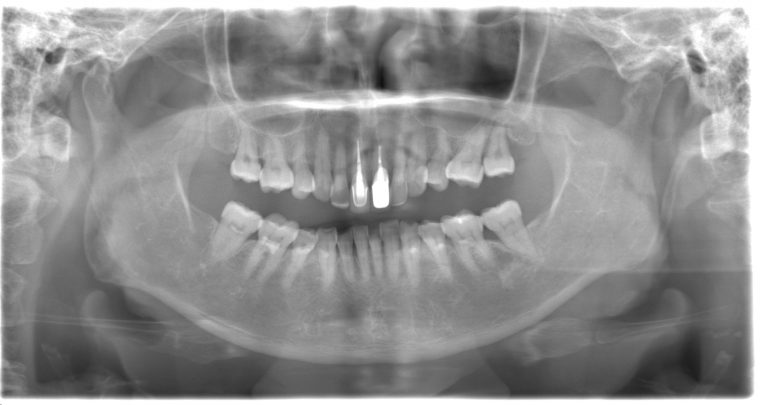

レントゲン写真

症例

特記事項 ・65年前に矯正治療をしてから歯をずっと大切にしてきたので、なるべく抜歯はしたくない。

・上の前歯は10年前にお孫さんがぶつかってきて、神経の治療をした。

・食いしばりをする癖がある為ナイトガード(夜間につける歯を保護するマウスピース)を作製し使用して頂いている。

担当者所見 左上は歯ぐきがかなり腫れていたが、歯石除去とホームケア(歯ブラシ、歯間ブラシSサイズ、ミクリンタフトブラシ)と抗生物質(軟膏)により腫れが落ち着いた。

それに加え、過度な力がかからないよう、ナイトガードを毎日使って頂くことと、日中の食いしばりにも気をつけてもらうようにした。

これは上の前歯を守るためのものでもあるので、必ず使用して頂いています。(上の前歯は神経がない為栄養が行き届かないので神経がある歯に比べ脆く根っこにヒビが入りやすい)

そして現在は定期検診で毎回異常がないか確認し、ホームケアではなかなか届かない歯周ポケット内のクリーニングを行っています。一度骨が溶けてしまっている為、歯周ポケットは残りますが、その後再発することは今のところなく、定期検診で今後もしっかり管理していきます。